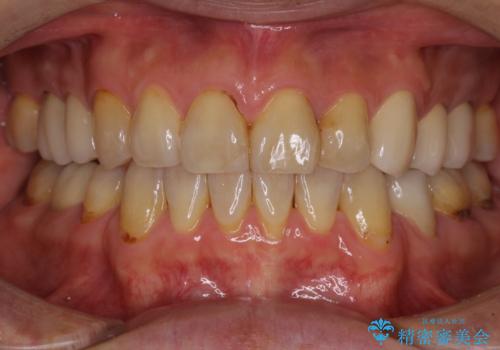

- むし歯による奥歯の痛みを気にして来院された患者様です。

神経にまでむし歯の及んでいる歯や、既に根管治療がされている歯に痛みがあったため、まずは根管治療を行うこととしました。

その後、以前行った抜歯矯正の後戻りをインビザライン・ライトにより改善し、むし歯や銀歯はオールセラミッククラウンにて補綴治療することとしました。

痛みは速やかに引き、銀歯や黒く変色したむし歯がセラミッククラウンで自然な色合いに仕上がり、患者様には大変満足していただきました。